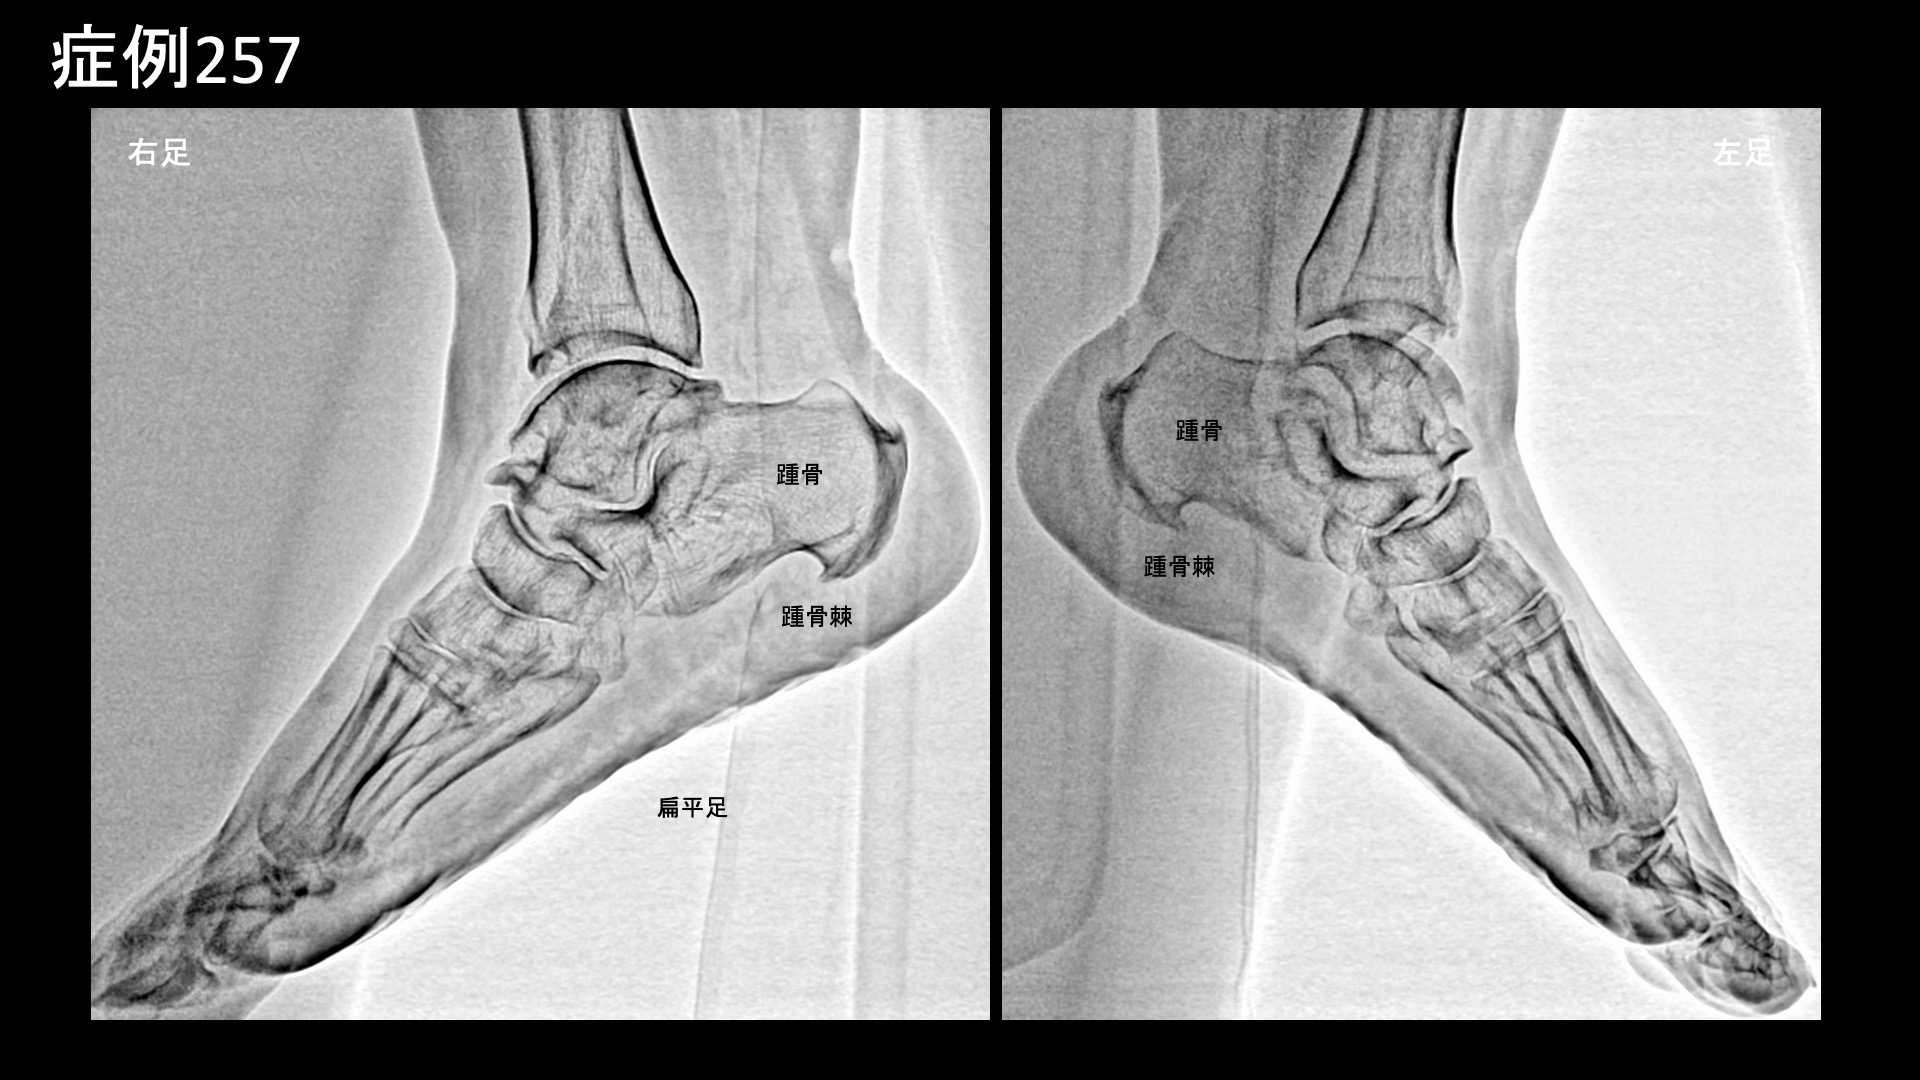

エコー検査では両膝とも水が溜まっており、モヤモヤ血管を反映した異常血流信号も内外にみられました。レントゲン検査では、両膝とも進行性の関節変形(KL分類3程度)を認めたほか、両足関節にも中等度の変形性変化を、足部では扁平足および踵骨棘を認めました。

両膝、両足首、左踵骨内側隆起に一致して圧痛を認めました。以上より、両膝関節および両足関節の変形性関節症、左足底筋膜炎と診断しました。重症度が高く、一定の症状が残存する可能性があること、再発リスクが高いこと、肥満解消や靴・インソールの適正化など総合的に治療していく必要があることなどをご理解いただいたうえで微細動脈塞栓術(運動器カテーテル治療)を受けていただきました。